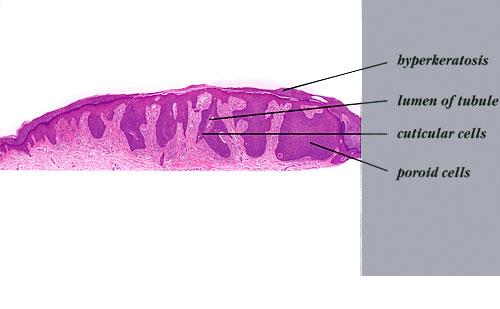

Clinically, hidroacanthoma simplex presents mostly in middle-aged and elderly individuals, preferentially in women as a solitary, hyperkeratotic plaque, with predilection for the extremities. Eccrine poroma occurs commonly as a solitary, slowly growing, skin-colored, or pigmented sometimes bright red, itchy, or painful pedunculated, sessile papule or nodule, situated mostly on the soles and palms of adults

Hidroacanthoma simplex shows sharply demarcated aggregations of cuboid to ovoid cells confined to the epidermis. Eccrine poroma reveals aggregations of uniform basaloid cells that radiate from the basal layer of the epidermis into the dermis . Dermal duct tumor consists of several sharply circumscribed, mainly dermal nodules composed of poroid and cuticular cells. Ductal structures are frequently observed. Poroid hidradenoma is characterized by intradermal, solid, and cystic aggregations of poroid cells.